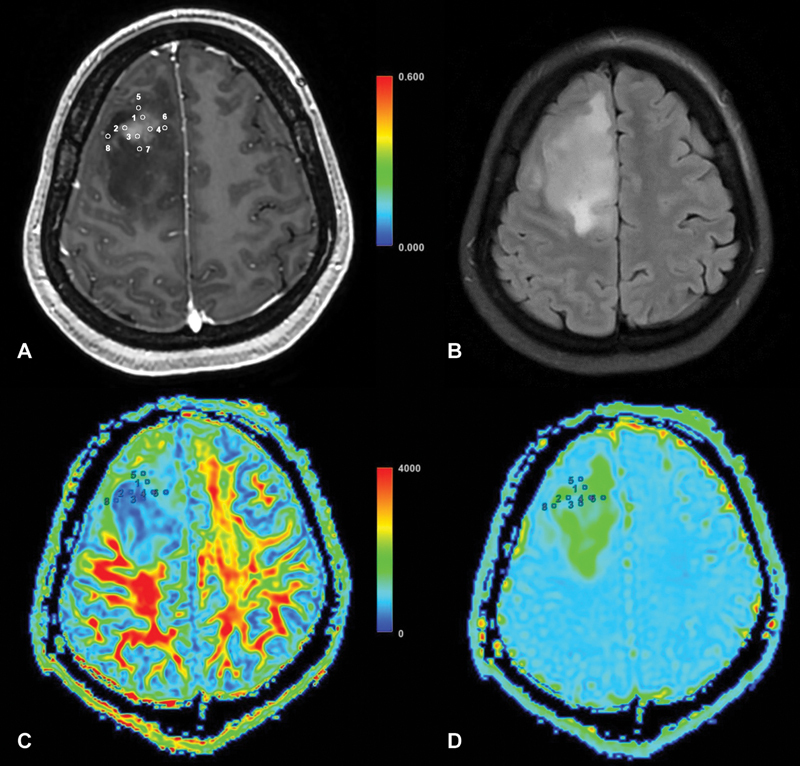

脑肿瘤,包括一系列肿瘤疾病,显著影响患者的发病率和死亡率。区分高级别胶质瘤(HGGs)和孤立性脑转移瘤(SBMs)对于定制临床管理至关重要。传统的结构磁共振成像(MRI)面临着这种分化的挑战,导致了先进成像模式的探索,如扩散张量成像(DTI)。材料和方法在这项前瞻性研究中,41例孤立性增强脑病变患者接受了组织病理学证实的全切除或次全切除。采用3-Tesla MRI扫描仪进行成像,并分析DTI数据的指标,包括平均扩散系数、分数各向异性(FA)、轴向扩散系数、径向扩散系数以及平面、球形和线性(CL)各向异性系数。结果HGG和SBM的瘤周FA和CL差异有统计学意义(p = 0.0217和p = 0.039)。瘤周FA和CL鉴别HGG和SBM的曲线下面积分别为0.2791和0.6984。其他扩散指标无显著差异。结论本研究有助于理解dti衍生的HGG和SBM分化指标。肿瘤周围FA和CL有望作为潜在的鉴别因子,为脑肿瘤患者的临床决策和治疗计划提供见解。未来更大规模的研究和先进的扩散成像技术可以进一步完善这些发现。

Background  Brain tumors, encompassing a spectrum of neoplastic disorders, significantly impact patient morbidity and mortality. Distinguishing between high-grade gliomas (HGGs) and solitary brain metastases (SBMs) is crucial for tailored clinical management. Conventional structural magnetic resonance imaging (MRI) faces challenges in this differentiation, leading to the exploration of advanced imaging modalities such as diffusion tensor imaging (DTI). Materials and Methods  In this prospective study, 41 patients with solitary enhancing brain lesions underwent total or subtotal resection, confirmed by histopathology. Imaging involved a 3-Tesla MRI scanner, and DTI data were analyzed for metrics including mean diffusivity, fractional anisotropy (FA), axial diffusivity, radial diffusivity, as well as planar, spherical, and linear (CL) anisotropy coefficients. Results  Peritumoral FA and CL exhibited significant differences ( p  = 0.0217 and p  = 0.039, respectively) between HGG and SBM. The area under the curve for peritumoral FA and CL in differentiating HGG and SBM were 0.2791 and 0.6984, respectively. No significant differences were observed in the other diffusion metrics. Conclusion  This study contributes to understanding DTI-derived metrics for HGG and SBM differentiation. Peritumoral FA and CL show promise as potential discriminators, offering insights for enhanced clinical decision-making and treatment planning in brain tumor patients. Future research with larger cohorts and advanced diffusion imaging techniques could further refine these findings.